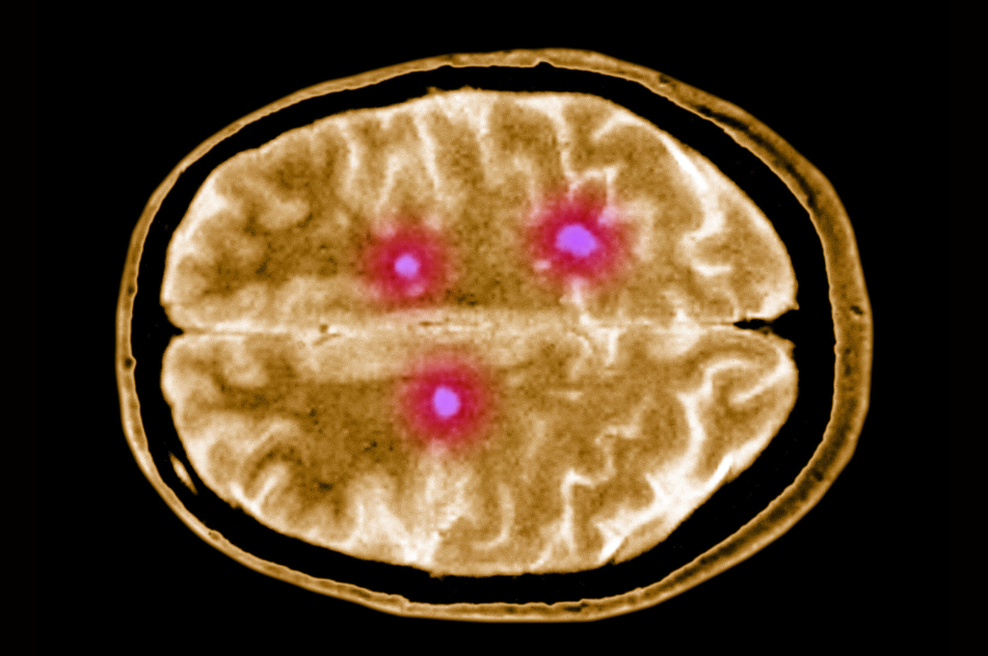

Multipla skleroza (MS) je kronična bolezen centralnega živčnega sistema, ki nastane kot posledica propadanja ovojnic živčnih vlaken, ki ščitijo nevrone v hrbtenjači in možganih. Bolezen ni ozdravljiva, a pravočasno odkrivanje lahko bistveno omili sam potek bolezni.